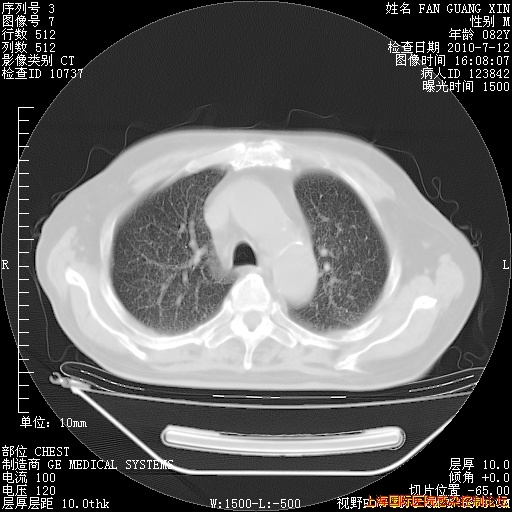

今天CT

整整相隔30天的肺部CT好像有所好转啊。甲强龙减量第3天,需要观察体温。

海管,自昨日你和我通完话后,不知您岳父消化道症状有无缓解?体温怎样?阅读7.12日胸部ct,个人认为目前激素治疗是有效的,甲强龙减量是适宜的。因在抗痨治疗,需密切观察肝功、肾功能和血常规。不过,老年、长期住院和大量使用激素,很担心菌群失调发生